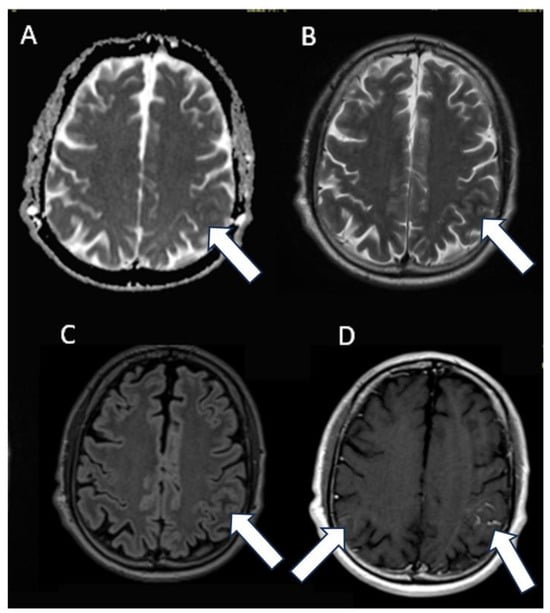

A 60-year-old Caucasian male presented with a secondary generalized focal motor seizure that caused post-ictal right hyposthenia, which resolved after 2 days. Neurological examination showed a slight leveling of the left lower limb during the Mingazzini maneuver, hyperelicitable osteotendinous reflexes in the four limbs with anisoreflexia left > right, pathological Babinski’s sign on the right, and hypopallesthesia of the lower limbs prevalent on the right with a cranio-caudal gradient. The patient had suffered from Waldenstrom macroglobulinemia 6 years before, but he recovered after treatment with Rituximab and Bendamustine. The patient did not have a history of epilepsy or any recent history of fever, vaccine, upper respiratory tract infection, abdominal symptoms, trauma, or travel. He suffered from psoriatic arthritis in treatment while taking Apremilast (300 mg × 2/day). At the time of presentation, the routine blood tests were unremarkable except for a slight increase in erythrocyte sedimentation rate (21 mm/h), lymphocytopenia (0.9 × 102/μL), and thrombocytopenia (127 × 103 μL). An unenhanced brain CT scan at the clinical onset revealed faint hyperdensity in some left parietal subarachnoid spaces (SHSs), which replaced the physiological hypodensity of the liquor (Figure 1). Patients underwent MRI scan after 5 days that revealed pathological signal and leptomeningeal enhancement on both left and right parietal SHSs without diffusion restriction (Figure 2). Further MRI examination performed one week later was negative for spinal cord and radicular/cauda equina alterations (Figure 3) but confirmed the stability of leptomeningeal findings. Leptomeningeal contrast enhancement was suspected for leptomeningitis, post-ictal hyperemia, and metastasis. After 20 days, the patient also underwent a total body CT scan to exclude any primary malignancies. Peripheral blood tumor marker (CEA, aFP, CA19-9, CA125, TPA, PSA, NSE, CYFRA), infective (HSV, HZV, JVC, EBV), and autoimmunity (anti-dsDNA, anti-RNP, anti-Sm) tests were negative. More than one month after the onset, cerebrospinal fluid (CSF) analysis documented the presence of monoclonal bands (light chain k, IgM) with elevated IgM index (0.45) calculated by [CSF IgM (mg/L)/serum IgM (g/L)]/[CSF albumin (mg/L)/serum albumin (g/L)] that is [1.89 (mg/L)/7.13 (g/L)]/[28.3 (mg/L)/48 (g/L)]. CSF flow cytometry revealed 2527 cells and 850 lymphocytes (33.64%). Among CSF lymphocytes, 87% of them were CD3+ CD5 +, while only 8% of them were CD19+ CD20+. The CSF tests did not reveal the presence of infectious meningitis (HSV1, HSV1, EBV, Adenovirus, Enterovirus, Parechovirus). The polymerase chain reaction test was negative for the L265P mutation in the MYD88 gene in both CSF and blood samples. CSF and MRI findings, along with the history of WM, were used to suggest the diagnosis of BNS within 2 months of the clinical onset (diagnostic timeline, Scheme 1). Therefore, brain tissue biopsy was not performed. A treatment with ibrutinib (140 mg three times daily) was initiated for the patient and is still receiving it. During a 1-year follow-up, there have been no new neurological signs or symptoms. The latest brain MRI showed a new subcortical left parietal lesion (18 mm) that was suspected to be caused by neoplastic cells infiltrating white matter vessels. Despite this, the spectroscopy map did not reveal any abnormal metabolic peaks in the lesion (Figure 4). The patient accepted the diagnosis and started and followed the therapy correctly. Despite his thrombocytopenia worsening, he tolerated the treatment well.

Figure 2. MRI axial images: (A) apparent diffusion coefficient (ADC) map, (B) T2-weightd image, (C) fluid-attenuated inversion recovery (FLAIR) image, and (D) post-contrast T1-weighted image. MRI imaging confirmed the abnormal signal (arrows) of subarachnoid spaces in left parietal region associated not to diffusion restriction but to leptomeningeal contrast enhancement. Similar less evident findings are also on the right side (arrow).